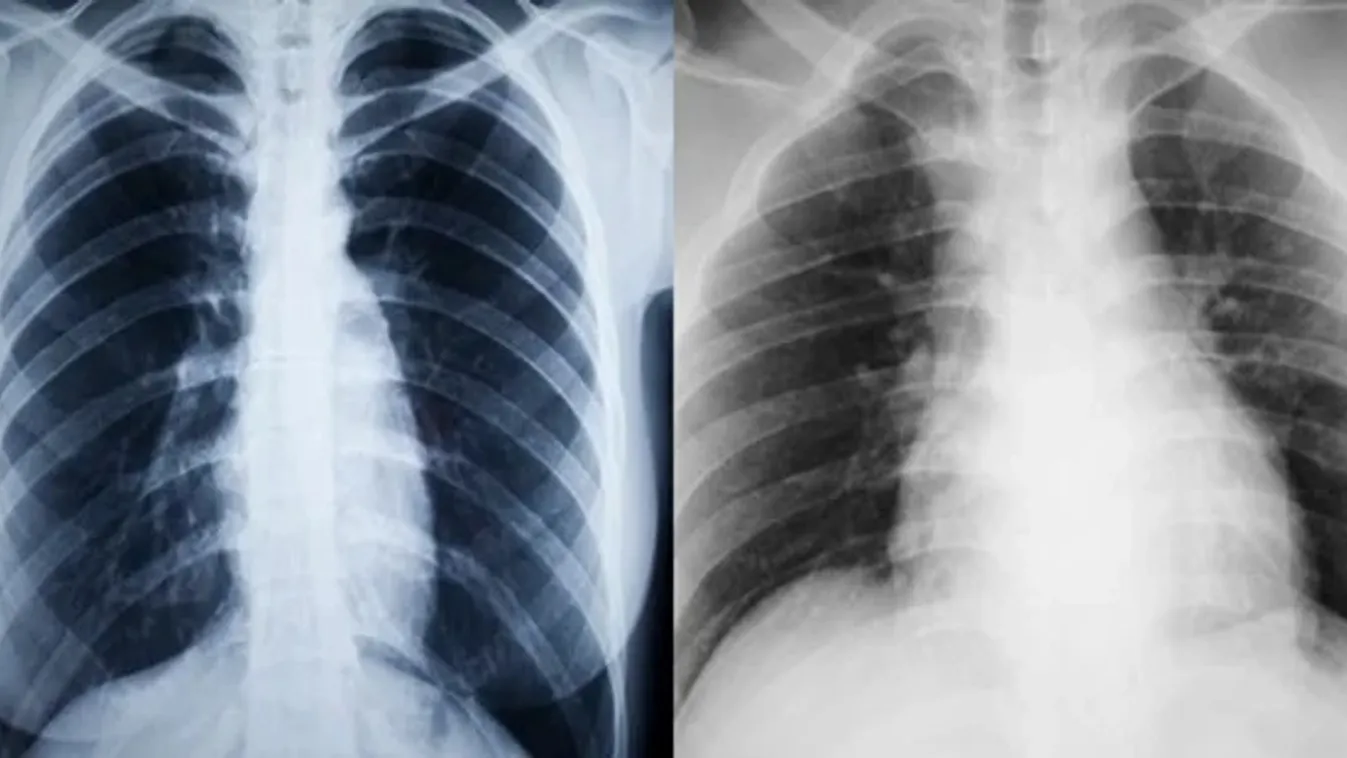

Egy szervtranszplantáción átesett michigani nő belehalt a Covid-19 szövődményeibe, miután egy koronavírus-fertőzött donor tüdejét ültették a szervezetébe – írja az American Journal of Transplantation tudományos szaklap.

A műtétre a michigani Ann Arbor Egyetemi Kórházban került sor 2020 közepén. A transzplantáció jól sikerült, de három nappal később a tüdő befogadójának hirtelen magas láza, alacsony vérnyomása és nehéz légzése lett, majd szeptikus sokk alakult ki nála. Az orvosokat ekkor többször is letesztelték koronavírusra a nőt, az eredmények pedig pozitívak lettek, sőt, a tüdejéből vett folyadékmintákban is kimutatták a vírus jelenlétét.